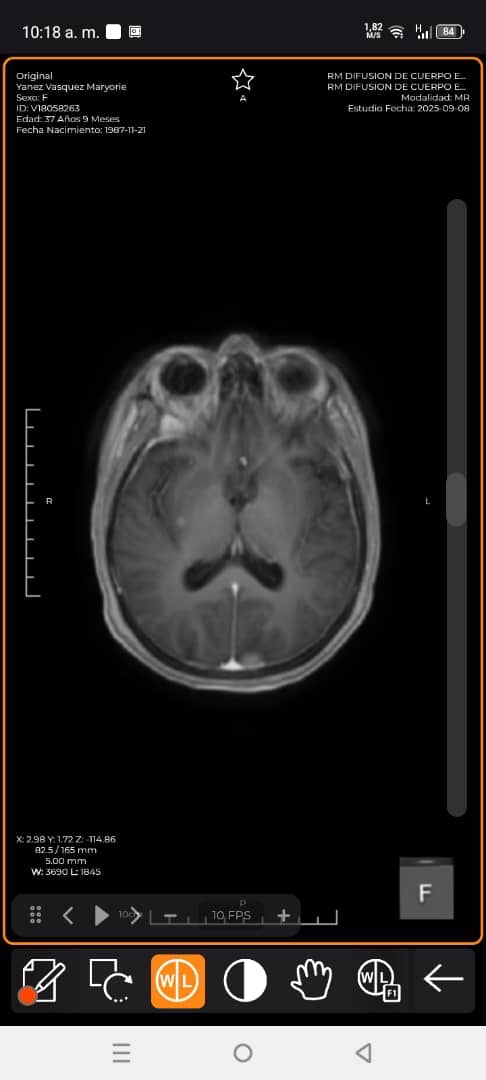

Hola mi nombre es Maryori Yanez , madre soltera y sustento de mi hogar , tengo dos hijos Jireth de 15 años y Enmanuel de 6 años . Actualmente me encuentro en cama debido a que he sigo diagnosticada con cancer de mamá con metástasis en el cerebro , pulmón, riñones e hígado . Necesito de suma urgencia realizarme 20 radioterapias , 10 en mi cerebro y 10 en mi columna para poder evitar mis convulsiones y volver a levantarme. Mis hijos y madre me necesitan , mi familia es de escasos recursos y no tenemos cómo cubrir los gastos para realizarme mis estudios . Les agradecería su ayuda , Dios se los multiplicara .